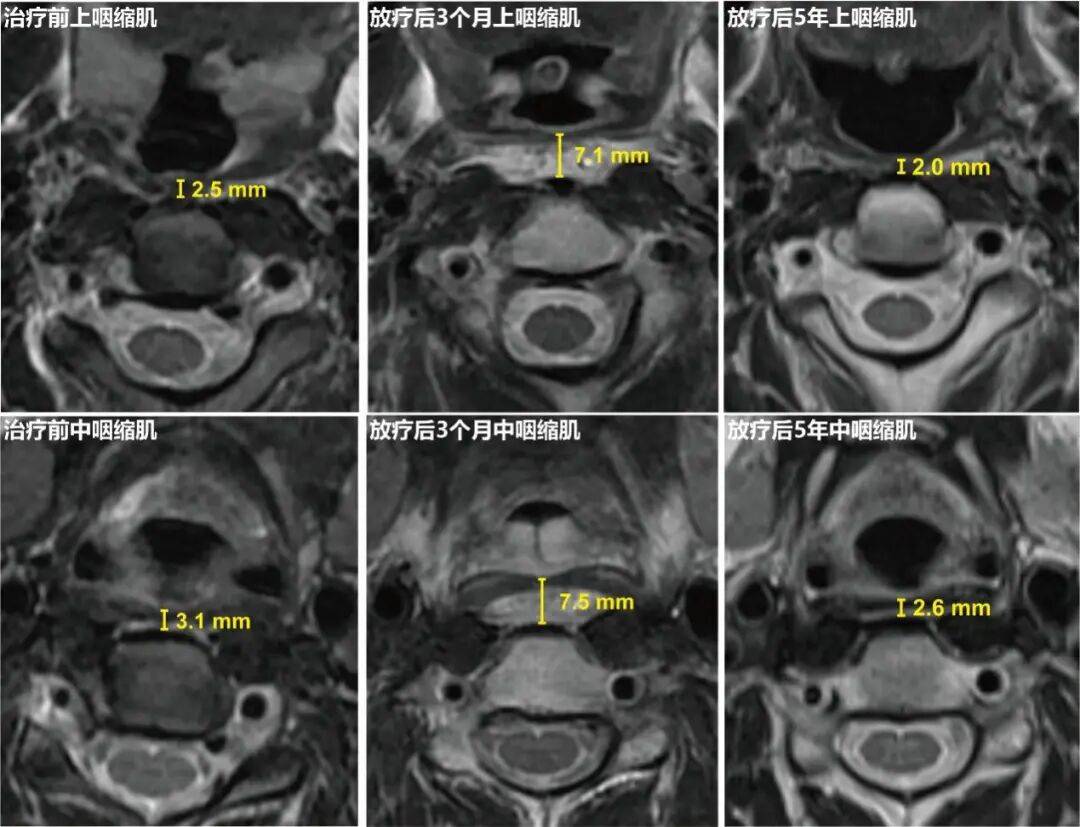

“内侧组咽后区豁免放疗”将咽缩肌接受>50Gy剂量的照射体积百分比由标准组的63%大幅降至8%。这种剂量学的优化转化为了明确的组织病理学获益。基于MRI的咽缩肌厚度动态测量结果显示,对比标准放疗组,内侧组咽后区豁免放疗组中,上咽缩肌和中咽缩肌早期水肿程度和晚期萎缩程度均明显减轻,具体表现为:放疗后3个月上咽缩肌(4.96 vs. 5.09 mm, P=0.04)和中咽缩肌(5.39 vs. 5.56 mm, P=0.03)的平均厚度更薄,以及放疗后5年上咽缩肌(1.80 vs. 1.65 mm, P=0.005)和咽中缩肌(2.34 vs. 2.15 mm, P=0.01)平均厚度更厚。

图3:治疗前、放疗后3个月及放疗后5年的上咽缩肌和中咽缩肌厚度